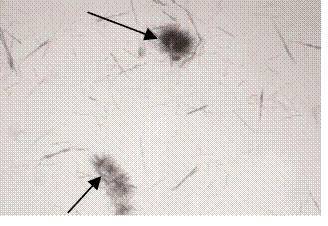

15、箭头所指细胞内结构的名称:纤维丝(如棉花丝等)

10、箭头所指细胞内结构的名称:纤维丝